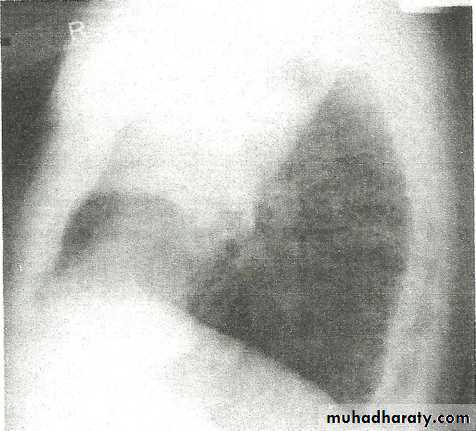

• LOBAR PNEUMONIA

Right lower lobe consolidation - PA. Dense opacification in the right lower zone with effacement of the outline of the right hemidiaphragm.